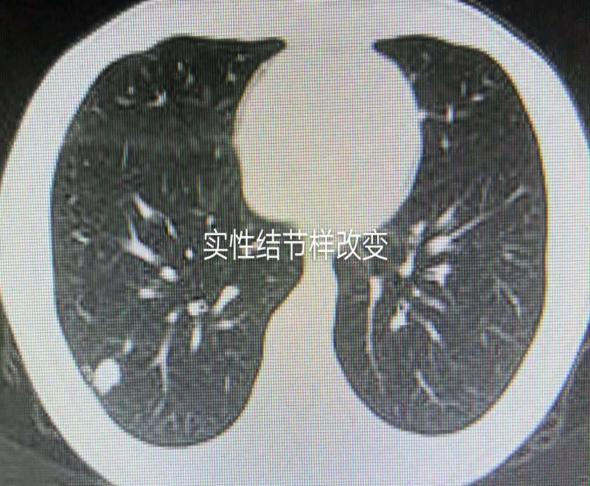

肺部小结节是胸外科的一种常见病,是指在肺部组织上出现的单一的或者多发的、直径等于或小于2 cm的结节样改变,在CT影像上多表现为磨玻璃样改变,也可以是实性结节样改变。其基本病理改变是由多核巨细胞、淋巴细胞、类上皮细胞共同组成的肉芽肿。在临床上,此类患者大多没有任何症状,少数会出现咳嗽、咳痰和胸疼等症状,肺部小结节病变性质不同,治疗方案差异很大,如果不能早期发现和及时有效的诊治干预,随着病情发展,很可能会发展成为恶性结节或者肺癌,危及患者的生命。

肺部小结节在CT上的表现通常是肺部磨玻璃影(GGO),其实质上是一种非特异性肺实质改变,在CT影像上表现为组织密度与透光度降低,但并不是癌组织的特异征象,因为在良性病变中也会出现此类征象,例如:良性肿瘤、感染性病变、纤维化改变等。有关研究表明[1],GGO的密度变化主要与肺泡与组织的密度、血管外的体液量、肺血容量等有关,而且受诸多其他因素的干扰。GGO结节多出现于炎性改变周围,有些也出现在肺癌组织周围。因此,早期采取有效的诊断技术对GGO进行定性分析是尤为必要的。

在临床诊疗中,根据CT影像上的密度差异,可将GGO结节影分为单纯GGO结节影和混合GGO结节影,前者在CT影像上显示密度较淡,没有实性密度成分,多为良性结节,一般与炎症、出血有关;后者是在磨玻璃密度影的背景下混杂有少量实性密度成分,多为恶性结节,一般与癌细胞不典型增生、浸润性生长有关。